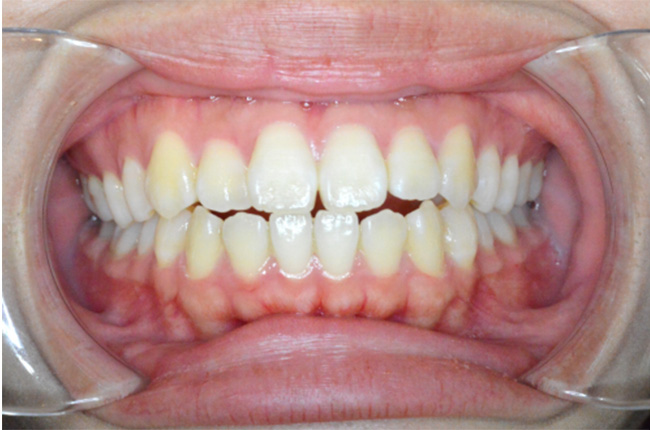

治療終了時

| 主訴 | 口元が出ている |

|---|---|

| 治療方法 | 上下顎小臼歯4本抜歯、ワイヤー矯正 |

| 治療内容 | 抜歯のスペースを使用して、上下前歯を後退させた |

| 治療期間 | 2年1ヵ月 |

| 治療費 | 979,000円(矯正装置・調整料・リテーナー・歯科矯正用アンカースクリュー・矯正治療後2年間経過観察料を含む) ※2025年10月以前の料金となります。 |

| 年齢 | 20代 |

| リスク・ 副作用 |

痛み、歯根吸収、歯肉退縮、虫歯、後戻り |